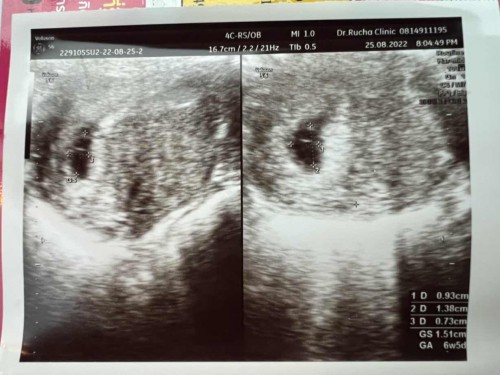

ทำไมในใบอัลตร้าซาวเขียนแค่ 6w5dคะ

หมอบอกได้ยินเสียงหัวใจมั้ยคะ